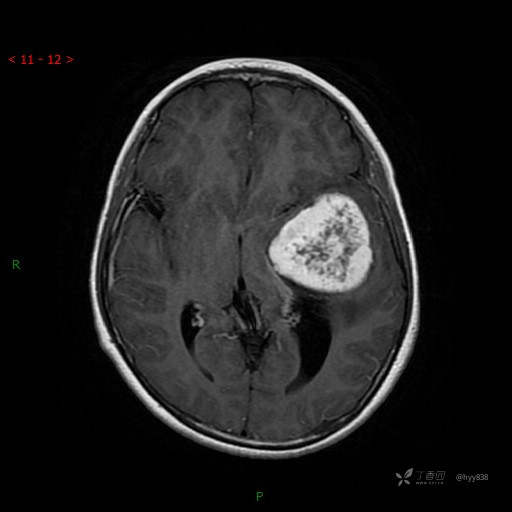

“典藏”病例分享。10岁儿童,头痛头晕一周余,CT、MRI 都有---结果公布~

患者年龄:10岁

主诉:头痛头晕一周余

简要病史:患者于一周前无明显诱因开始出现头痛头晕,无恶心呕吐,无肢体抽搐,无寒颤高热,无腹胀腹泻,无视力下降及视野缺损,上述症状休息后可稍缓解,未引起重视。 2天前患者头痛头晕不适加重,伴有恶心感,无呕吐,遂到当地人民医院行头颅CT检查示:左侧颞部占位性病变,今日家属为求进一步治疗,来我院门诊求治。门诊拟“左侧颞部占位性病变”收入我科。 患病以来,患者精神、饮食、睡眠尚欠佳,大小便如常,体力体重无明显变化。

临床诊断:左侧颞部占位

颅脑CT扫描